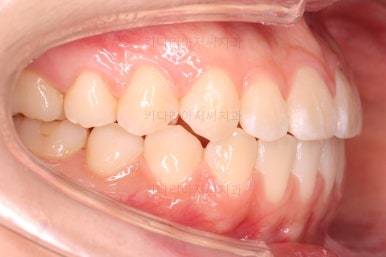

각설하고 위의 사진들은 부산치아교정잘하는곳 키다리아저씨치과에서 처음 내원하셨을 때의 사진입니다.

그리고 오른쪽 위 송곳니가 덧니처럼 볼록하여 웃거나 말할 때 자신감 있게 입을 벌리지 못하고 있었어요.

아랫니는 크게 심하지 않았고 윗니 앞니쪽에 치열이 삐뚤한 것을 볼 수 있어요.

그리고 위아랫니의 중앙선도 어긋나 있는 것으로 봐서 왼쪽과 오른쪽의 교합 자체도 다르고 문제가 있음을 알 수 있었어요.

각각 왼쪽, 오른쪽의 교합의 모습입니다.

가장 좋은 교합은 위아래 치아들이 지그재그로 톱니바퀴 물리듯이 맞아들어가야 하는데 오른쪽 사진들 보면 중간중간 빈틈도 많이 보여요.

이런 교합은 장기적으로 치아 수명을 단축시킬 수 있습니다.